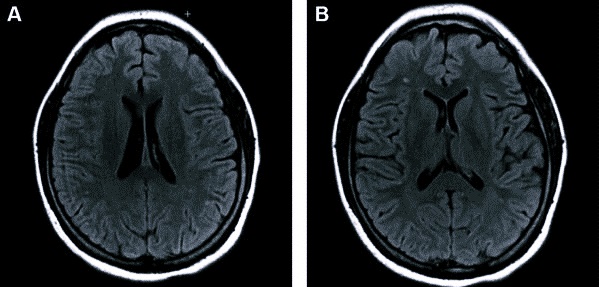

Умеренные диффузные изменения белого вещества головного мозга (БЭА) могут свидетельствовать о различных патологиях, включая сосудистые заболевания, демиелинизирующие процессы и возрастные изменения. Врачи отмечают, что такие изменения часто сопровождаются симптомами, такими как головные боли, снижение когнитивных функций, ухудшение памяти и внимание. Для диагностики используются методы нейровизуализации, такие как МРТ, которые позволяют визуализировать изменения в структуре мозга. Лечение зависит от причины изменений и может включать медикаментозную терапию, физиотерапию и изменение образа жизни. Важно, чтобы пациенты своевременно обращались к специалистам, так как ранняя диагностика и адекватное лечение могут значительно улучшить качество жизни и замедлить прогрессирование заболеваний.

- магнитно-резонансная томография;

На МРТ пациента отправляют, если зафиксирована повышенная электрическая активность. Она свидетельствует о наличии патологии, которая будет заметна на томографическом снимке.